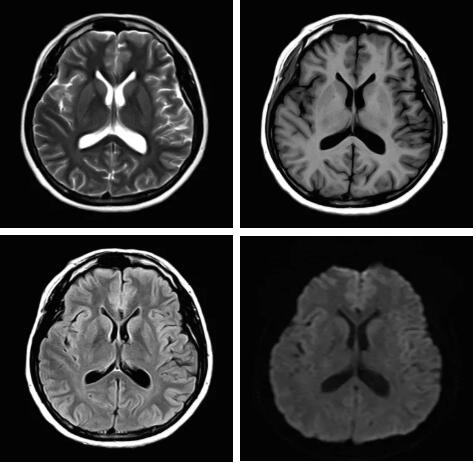

眾所周知,磁共振成像最核心的三個(gè)部分:磁體、梯度、射頻,此三部分為磁共振成像之魂,直接決定著磁共振成像的圖像質(zhì)量--圖像信噪比。各個(gè)廠家在磁共振成像提升圖像信噪比的道路上不斷探索和創(chuàng)新,致力于信噪比的提升,各個(gè)廠家側(cè)重點(diǎn)不同,在各自領(lǐng)域各有所長(zhǎng),在本世紀(jì)第二個(gè)十年,各個(gè)廠家都在做不同的嘗試和改進(jìn),例如:A廠家的“太空艙”技術(shù),旨在解決射頻發(fā)射和射頻接收的實(shí)時(shí)互補(bǔ)……;B廠家的ADC前置所謂的“全數(shù)字”技術(shù),旨在解決信號(hào)模數(shù)轉(zhuǎn)換的時(shí)間早晚……;C廠家的“光纖”技術(shù),旨在解決信號(hào)傳輸路徑的信號(hào)損失……;各家都在一定程度上解決了信號(hào)的損失,信噪比在一定程度上有所提升,但是并未從根本上解決信噪比大幅度提升。

佳能公司在2018年率先提出了Pure射頻成技術(shù),從源頭上解決信噪比的提升,著眼于全路徑、全成像鏈的優(yōu)化和改進(jìn)。

3.Pure射頻成像鏈

從成像源頭的磁體采用鍍膜新磁體高密度薄層鍍膜貼合技術(shù),獲得更好的磁場(chǎng)均勻度,奠定磁共振成像基礎(chǔ);采用3D RSCE微雕梯度精準(zhǔn)控制頻率和相位,輸出理想波形,實(shí)現(xiàn)渦流的“0”殘余,還原最真實(shí)的圖像信息;射頻接收端通過計(jì)算機(jī)人工智能對(duì)信號(hào)抗干擾處理,把信號(hào)放大并去除梯度、磁場(chǎng)等對(duì)信號(hào)干擾,再經(jīng)過二次人工智能信號(hào)識(shí)別,去除噪聲污染獲得純凈的信號(hào);通過Pure射頻成像鏈的優(yōu)化和改進(jìn)使信噪比提升40%,這是磁共振領(lǐng)域革命性的顛覆和改變。